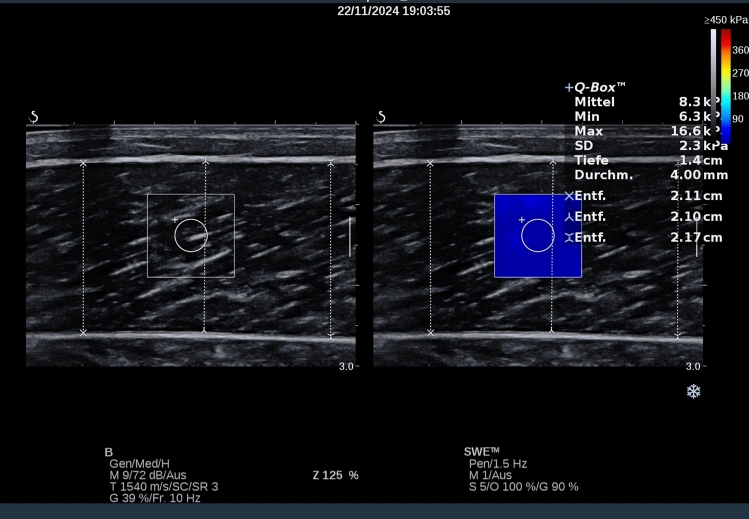

Methods: A total of 75 subjects participated in this double-blinded reliability evaluation. Besides muscle thickness assessments, lower legs' ST in the calf muscle and Achilles tendon (shear-wave elastography [SWE] and viscoelastic parameters [MyotonPRO], respectively) were correlated with ankle dorsiflexion ROM (knee-to-wall test [KtW]).

Results: Ultrasound image acquisition (i.e., muscle thickness and ST) and myotonometry showed intrasession reliability (ICC = 0.93-0.99 and 0.72-0.99, respectively) depending on the device. Only for MyotonPRO, there were meaningful systematic and random errors only for decrement (SEM = 0.002-10.629; MAE = 0.01-24.84). ROM showed ICC > 0.99, while for all parameters interday reliability declined (ICC = 0.395-0.88). Interrater objectivity showed ICC = 0.61-0.91 for ultrasound analysis and 0.66-0.96 for myotonometry. No agreement (ICC = 0-0.09) between different ST measurements was observed, while relationship between ST and ROM depended on the investigator (r = 0.21-0.26 versus r = - 0.02--0.07).